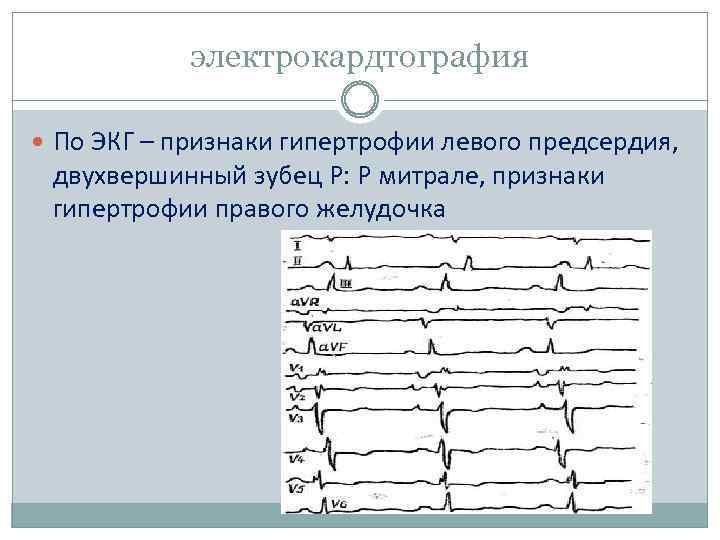

электрокардтография По ЭКГ – признаки гипертрофии левого предсердия, двухвершинный зубец Р: Р митрале, признаки гипертрофии правого желудочка